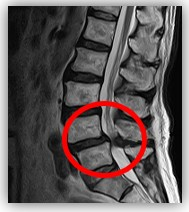

脊柱管狭窄症とは、脊柱管と呼ばれる脊椎骨の中にある神経組織が圧迫されることで引き起こされる疾患です。

脊柱管狭窄症は、脊柱管内にある脊髄や神経根に圧迫がかかることで、腰や脚の痛み、しびれ、などの症状が現れます。